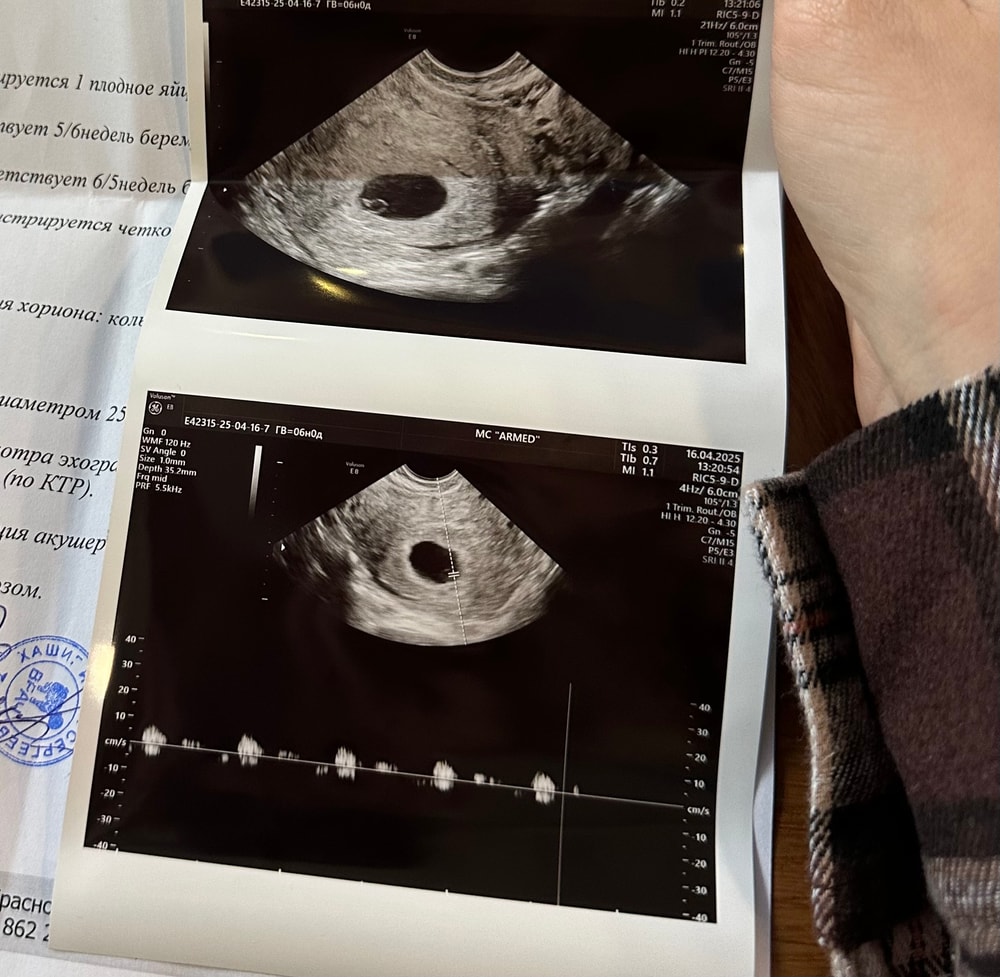

Мария в Благополучная беременность 8 месяцев Первое УЗИ УЗИ, КТГ, доплер Нашей первое узи 16.04,все хорошо,на сроке 5+6 услышали сердцебиение.Не верится,что я снова стану мамой 🥰 Посмотрите еще 20 записей на эту тему Отменить Ответить Толшина рубца в 32 недели Ктг плода Чаты Беременных Выберите чат: Январята-2026 Февралята-2026 Мартята-2026 Апрелята-2026 Майчата-2026 Июнята-2026 Июлята-2026 Августята-2026